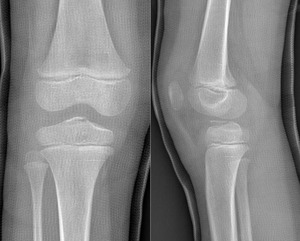

Plain anteroposterior and lateral radiographs demonstrated a bony fragment detached from the tibial plateau at the level of the tibial spine, consistent with a partially displaced, but not rotated, ACL avulsion fracture (Figure 1). The fracture was classified as a Type II Meyers and McKeever lesion based on radiographic features. Magnetic resonance imaging (MRI) confirmed the diagnosis, showing avulsion of the tibial spine with a fragment arising from the tibial eminence, associated bone marrow edema, and soft-tissue swelling. No meniscal tear or intermeniscal ligament entrapment, chondral lesion, collateral ligament injury, was detected (Figure 2).